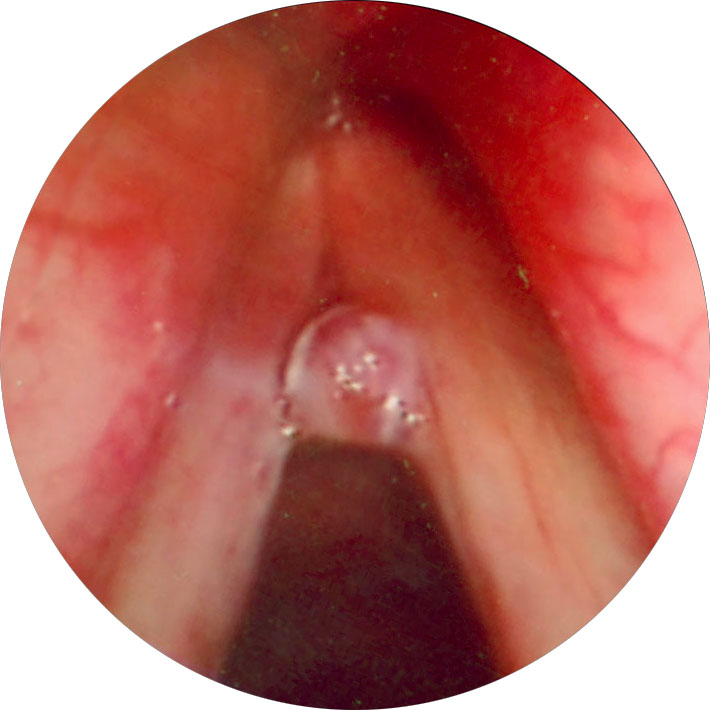

該技術(shù)采用生物低溫等離子摘除無精癥,在較低的溫度下,對無精癥進行消融摘除,不傷害正常的粘膜組織,有效減輕水腫與疼痛,來達到最終的治療目的,日本電子纖維喉鏡管徑小,圖像可放大,視野清晰,能在一定范圍內(nèi)隨意彎曲改變方向,發(fā)現(xiàn)隱蔽微小病變,順利處理前連合及聲帶邊緣下方的病變,摘取準(zhǔn)確,損傷小,術(shù)后反應(yīng)輕,較大息肉0.5~1.2cm可先經(jīng)間接喉鏡下摘除,殘余部分經(jīng)纖維喉鏡取出。較大息肉采用此法,一次完成手術(shù),效果顯著。

2、低溫消融術(shù)纖維喉鏡管徑小,圖像可放大,視野清晰,能在一定范圍內(nèi)隨意彎曲改變方向,發(fā)現(xiàn)隱蔽微小病變,順利處理前連合及聲帶邊緣下方的病變,摘取準(zhǔn)確,損傷小,術(shù)后反應(yīng)輕,較大息肉可先在間接喉鏡下摘除,殘余部分經(jīng)纖維喉鏡取出。較大息肉采用此法,一次完成手術(shù),效果良好。